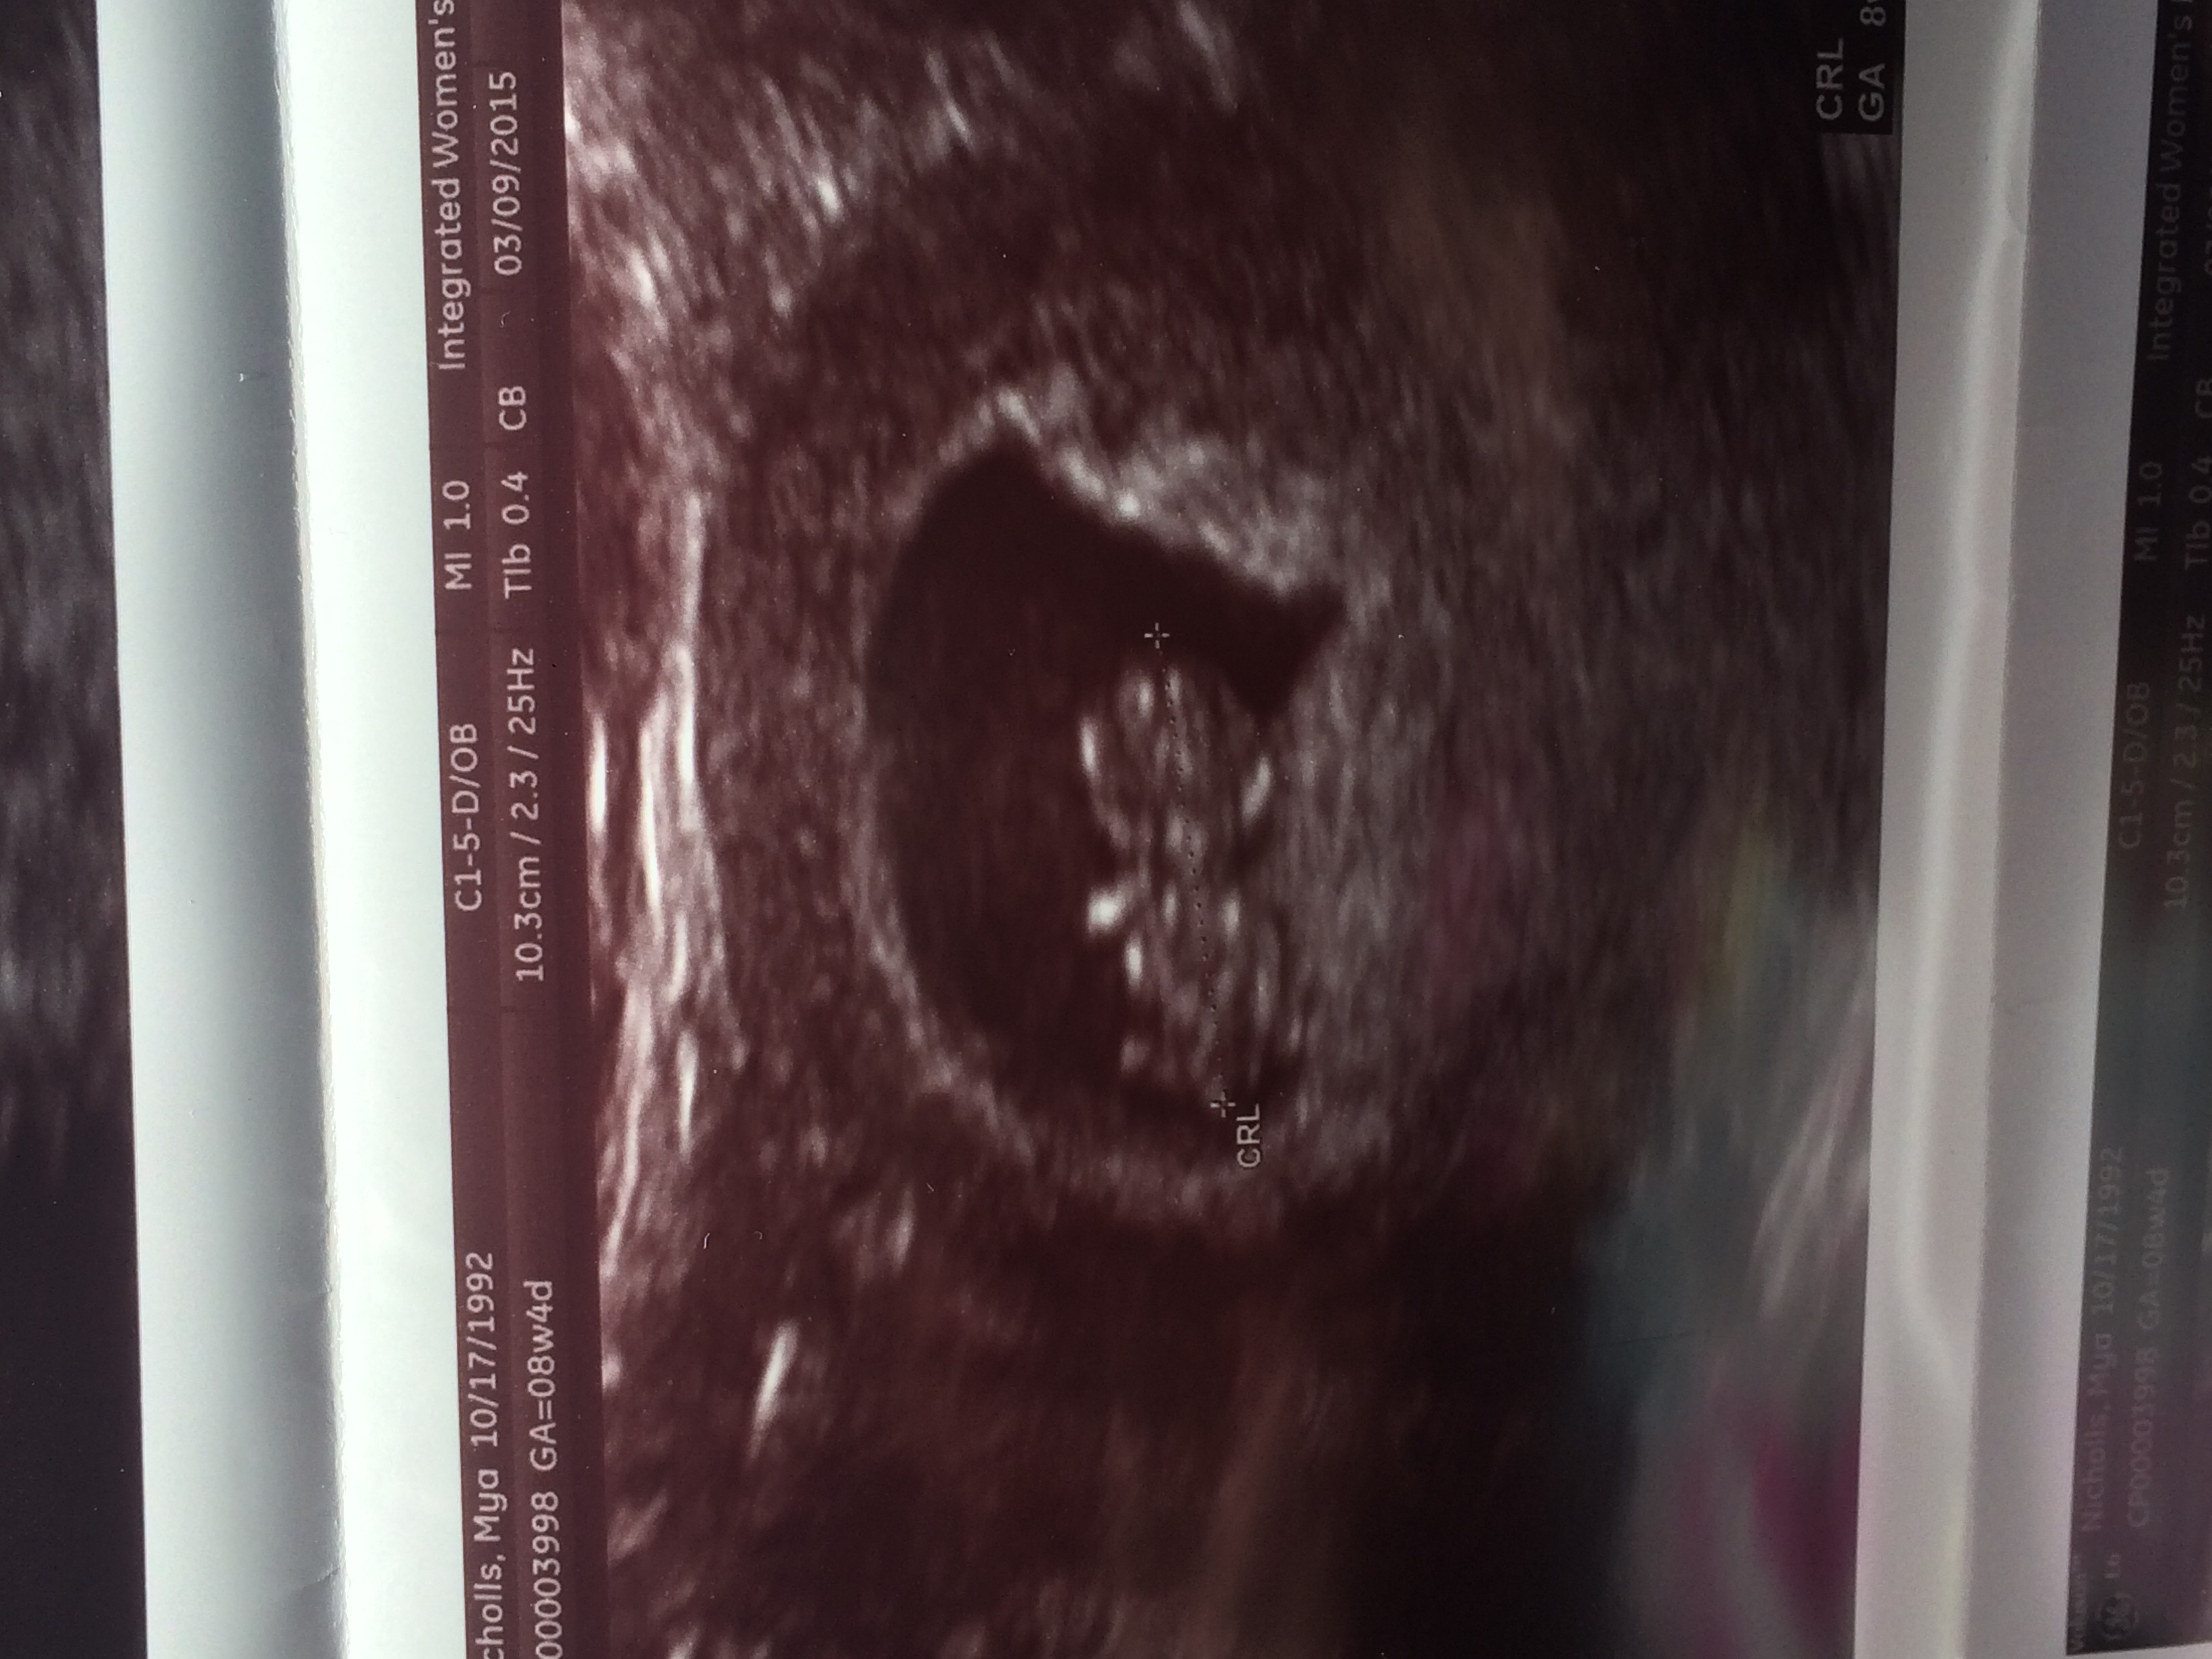

Just had our dating scan today! 8 weeks exactly! Here is cub's head & little arm/leg stumps! I have a cyst in an ovary but was told that should go away. This is our first!